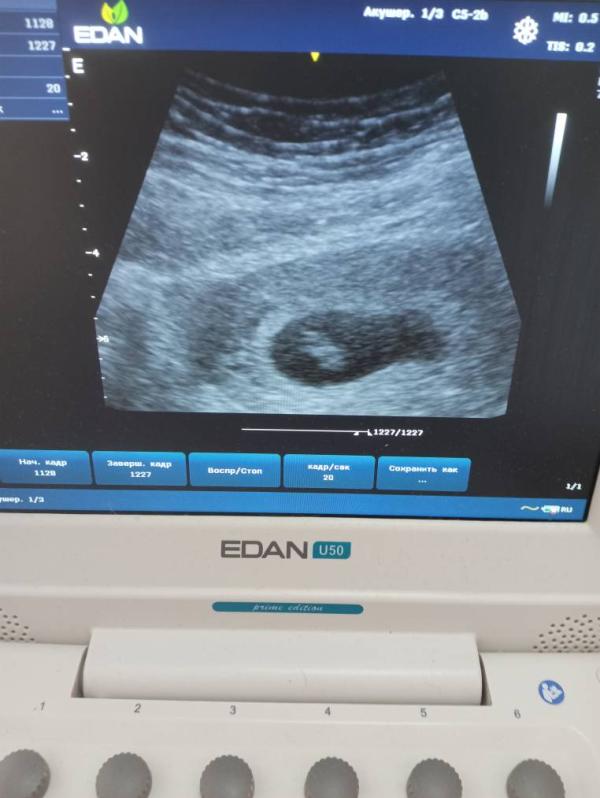

Муж увидел печеньку рыбки — что было дальше?

Муж увидел печеньку "рыбки" 😅😅😅

Кстати, да😄даже всматриваться не нужно😄

Господи, это же про плодное яйцо